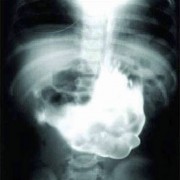

Можеби понекогаш се чувствувате виновно заради обилниот ручек што сте го изеле, но кога ќе видите што ставиле овие луѓе во својот стомак, ќе сфатите дека вие немате причина да се грижите. Барем не сте изеле батерии. Иако можеби имаат помалку калории, попрво би јаделе вкусни слатки со многу масти отколку киселински раствор. Луѓето имаат изедено некои многу чудни нешта…